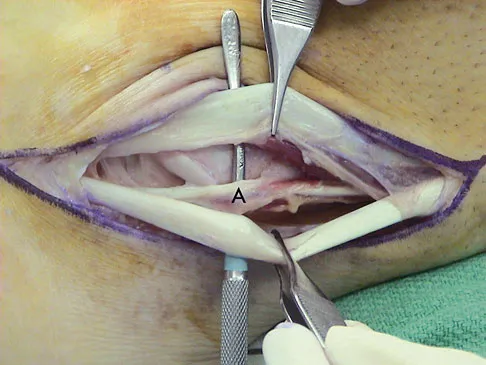

Question 66

A 35-year-old man is seen for evaluation of his left ankle following multiple previous ankle sprains and frequent episodes of the ankle giving way. Examination reveals marked laxity about the lateral ankle with associated tenderness along the peroneal tendons. Physical therapy, anti-inflammatory drugs, and supportive bracing have failed to provide relief. An MRI scan shows peroneal tenosynovitis and a possible tear. He elects to undergo a peroneal tendon repair and lateral ligament reconstruction. Which of the following best describes the structure labeled "A" in Figure 45?

Explanation